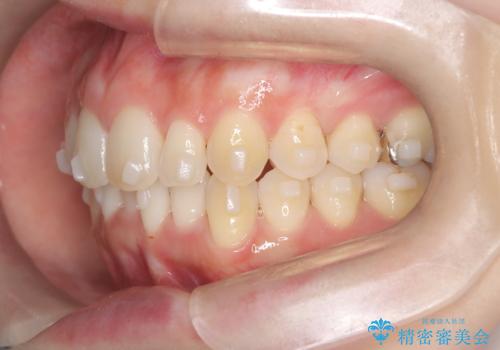

インビザラインで整えた前歯の歯並び

- 患者様は、上下前歯の歯列不正(ガタガタ)を主訴としてご来院されました。治療計画として、透明なマウスピース型矯正装置「インビザライン」を使用し、約2年の期間を見込んで前歯部の歯列を整える方針を立てました。特に下顎前歯に歯肉退縮のリスクがあるため、治療中にIPR(インタープロキシマルリダクション)を行い、歯間を適切に削ることで、過度な圧力を避け、歯肉退縮を防ぎながら配列を進めました。治療は慎重に進め、最終的にきれいで整った前歯の歯並びを目指しました。

インビザラインによる矯正治療は、患者様自身が装着するマウスピース型の装置を使用するため、装着時間の徹底が重要です。特に、下顎前歯の歯肉退縮を避けるため、IPRを施すことで歯間スペースを確保し、歯肉にかかる負担を減らしました。この方法により、歯並びを整えながらも歯肉の健康を保つことができます。治療期間中は定期的にチェックを行い、歯肉の状態や歯の動きを慎重に確認しました。また、治療後はリテーナーを装着して歯並びを維持し、安定させました。